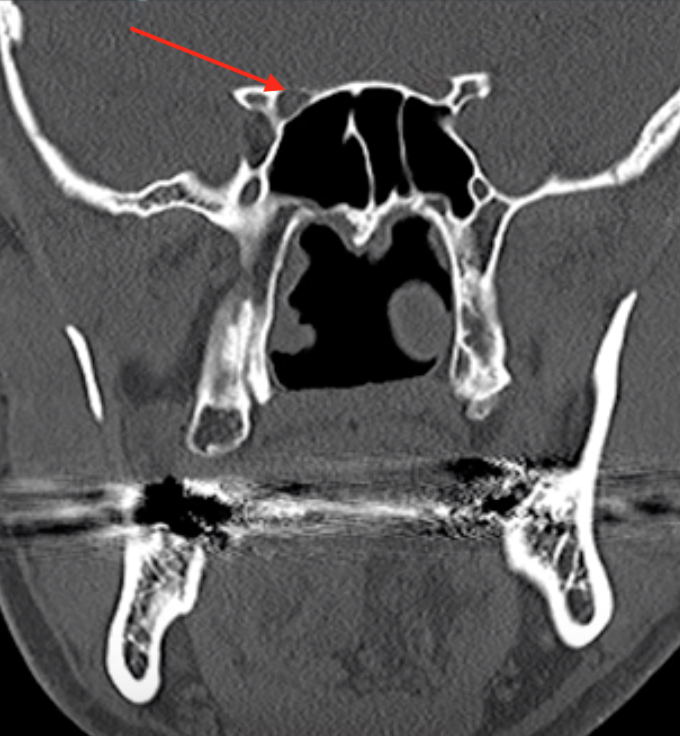

Optic Canal

• Structures passing through here:

• CN 1

• Ophthalmic artery

Superior Orbital Fissure

• CN 3, 4, 5-V1, 6

• Superior ophthalmic vein